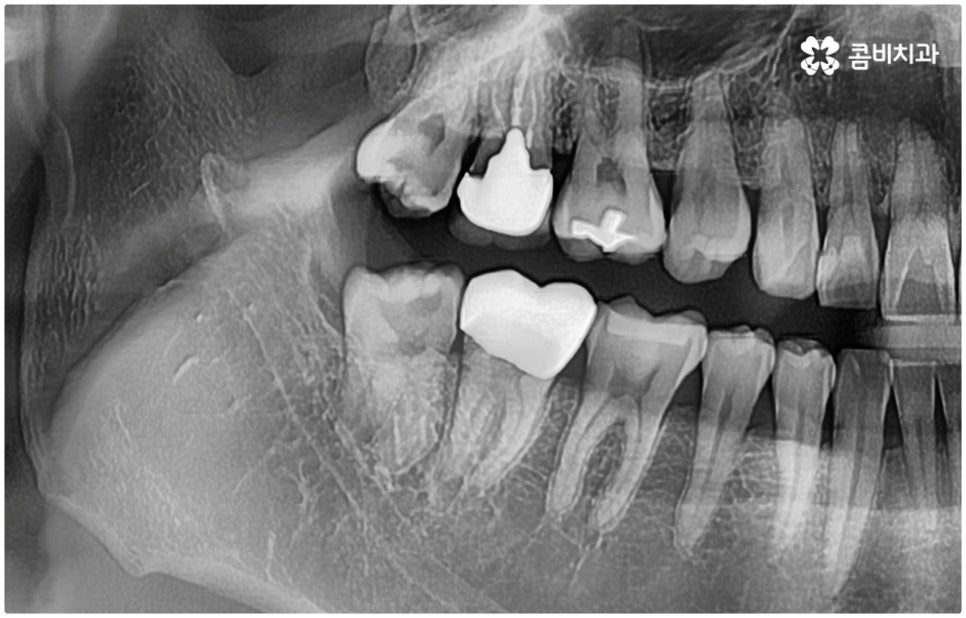

특히 매복 사랑니 중 잇몸 속에 전부 묻혀 있는 사랑니를 완전매복사랑니라고 부르는데 이 경우 누운 방향으로 자라나면서 앞 어금니 뿌리에 지속적인 압박을 가하여 신경을 누르기도 하고 치근을 흡수시키거나 치열이 앞쪽으로 쓰러지게 만들어 부정교합을 유발하기도 하며 드물게는 함치성 낭종이 생겨 턱뼈를 녹이는 상황까지 발생할 수도 있기 때문에 꼼꼼하게 검진을 하여 만약에 필요하다면 늦지 않게 발치 처치를 해 주어야 하는 거예요.

매복사랑니발치치과 를 선택할 때 어떤 것을 기준으로 고르는 것이 좋을까요? 사랑니가 완전히 매복되어 있다면 잇몸을 절개하고 상황에 따라 골삭제 후 치아를 조각내어 빼내줄 필요가 있는데 이러한 과정이 굉장히 까다롭기 때문에 먼저 환자분들의 사랑니 위치 및 뿌리의 형태, 인접 치아 구조, 주변 조직이나 신경 위치 등을 구체적으로 확인할 수 있는 3D CT와 같은 정밀 검진 장비를 갖추고 있는 매복사랑니발치치과 인지 체크해 보실 필요가 있어요.

하악 사랑니의 경우 하치조 신경을 건드리지 않도록 주의해야 하고 상악 사랑니의 경우 상악동 천공을 조심해야 하는데 이 때 환자분들의 상황 또한 개인마다 천차만별인 만큼 각각을 꼼꼼하게 살펴보고 섬세하게 발치 처치를 하기 위해 술자의 뛰어난 기술력 및 숙련도가 요구되므로 매복사랑니발치치과 의료진의 경력 사항을 면밀하게 살펴보시는 것도 도움이 될 거예요.